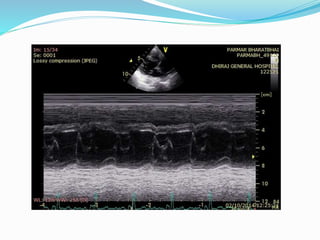

ECHOCARDIOGRAPHY

 2D echo:

 Pericardial thickening (TEE more sensitive)

 Normal RV and LV chamber size

 LA and RA enlargement

 Abnormal septal and posterior wall motion

 Paradoxical septal motion

 Premature opening of the pulmonic valve

 Dilated IVC without respiratory variation